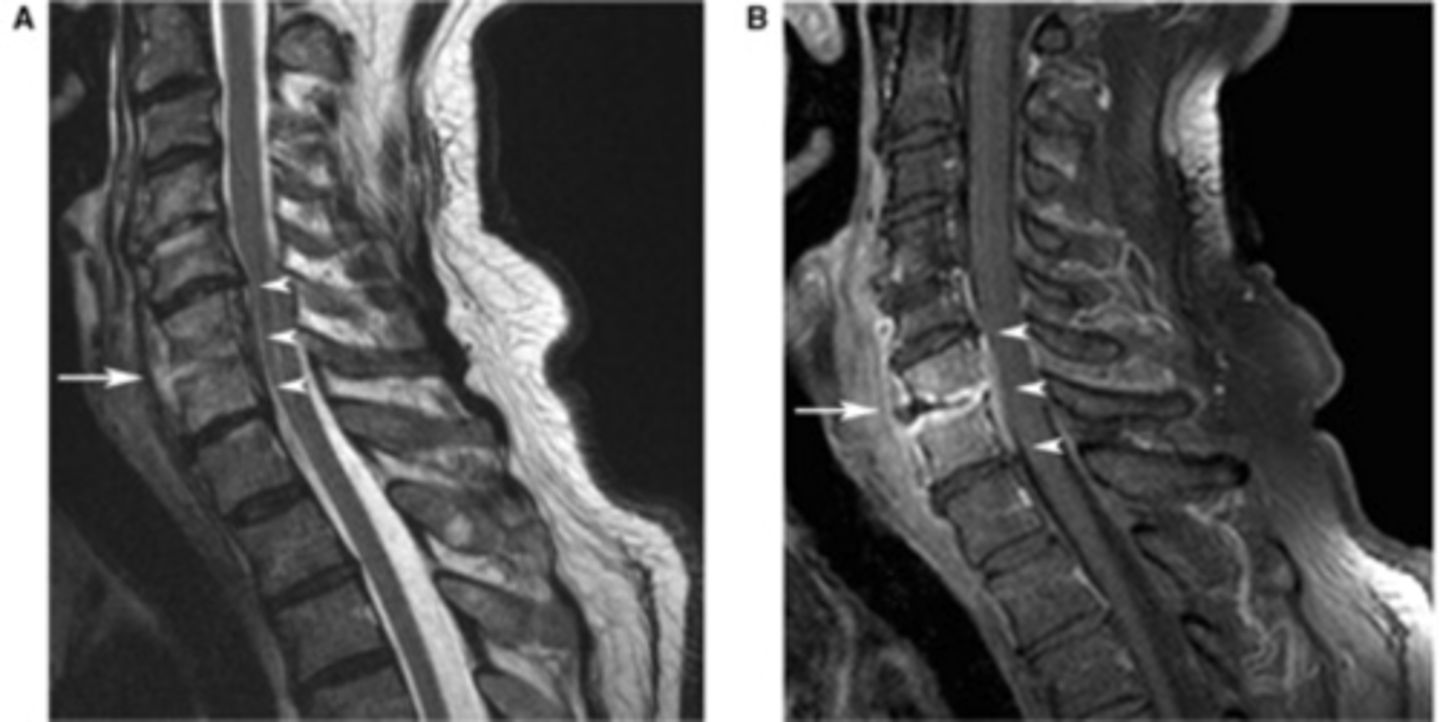

osteomyelitis MRI

infection of the bone and intervertebral discs

spine imaging

MRI- study of choice for spinal cord, intervertebral discs, compression of spinal nerves

herniated disks

degeneration of outer annular fibers, caused by acute compression of nerve root

MRI is study of choice

spinal stenosis

narrowing of the spinal canal or neural foramina, caused by soft tissue and bony abnormalities, congenital or acquired

MRI is study of choice